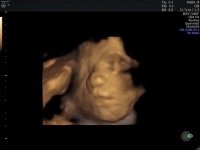

Lille i magen var veldig planlagt